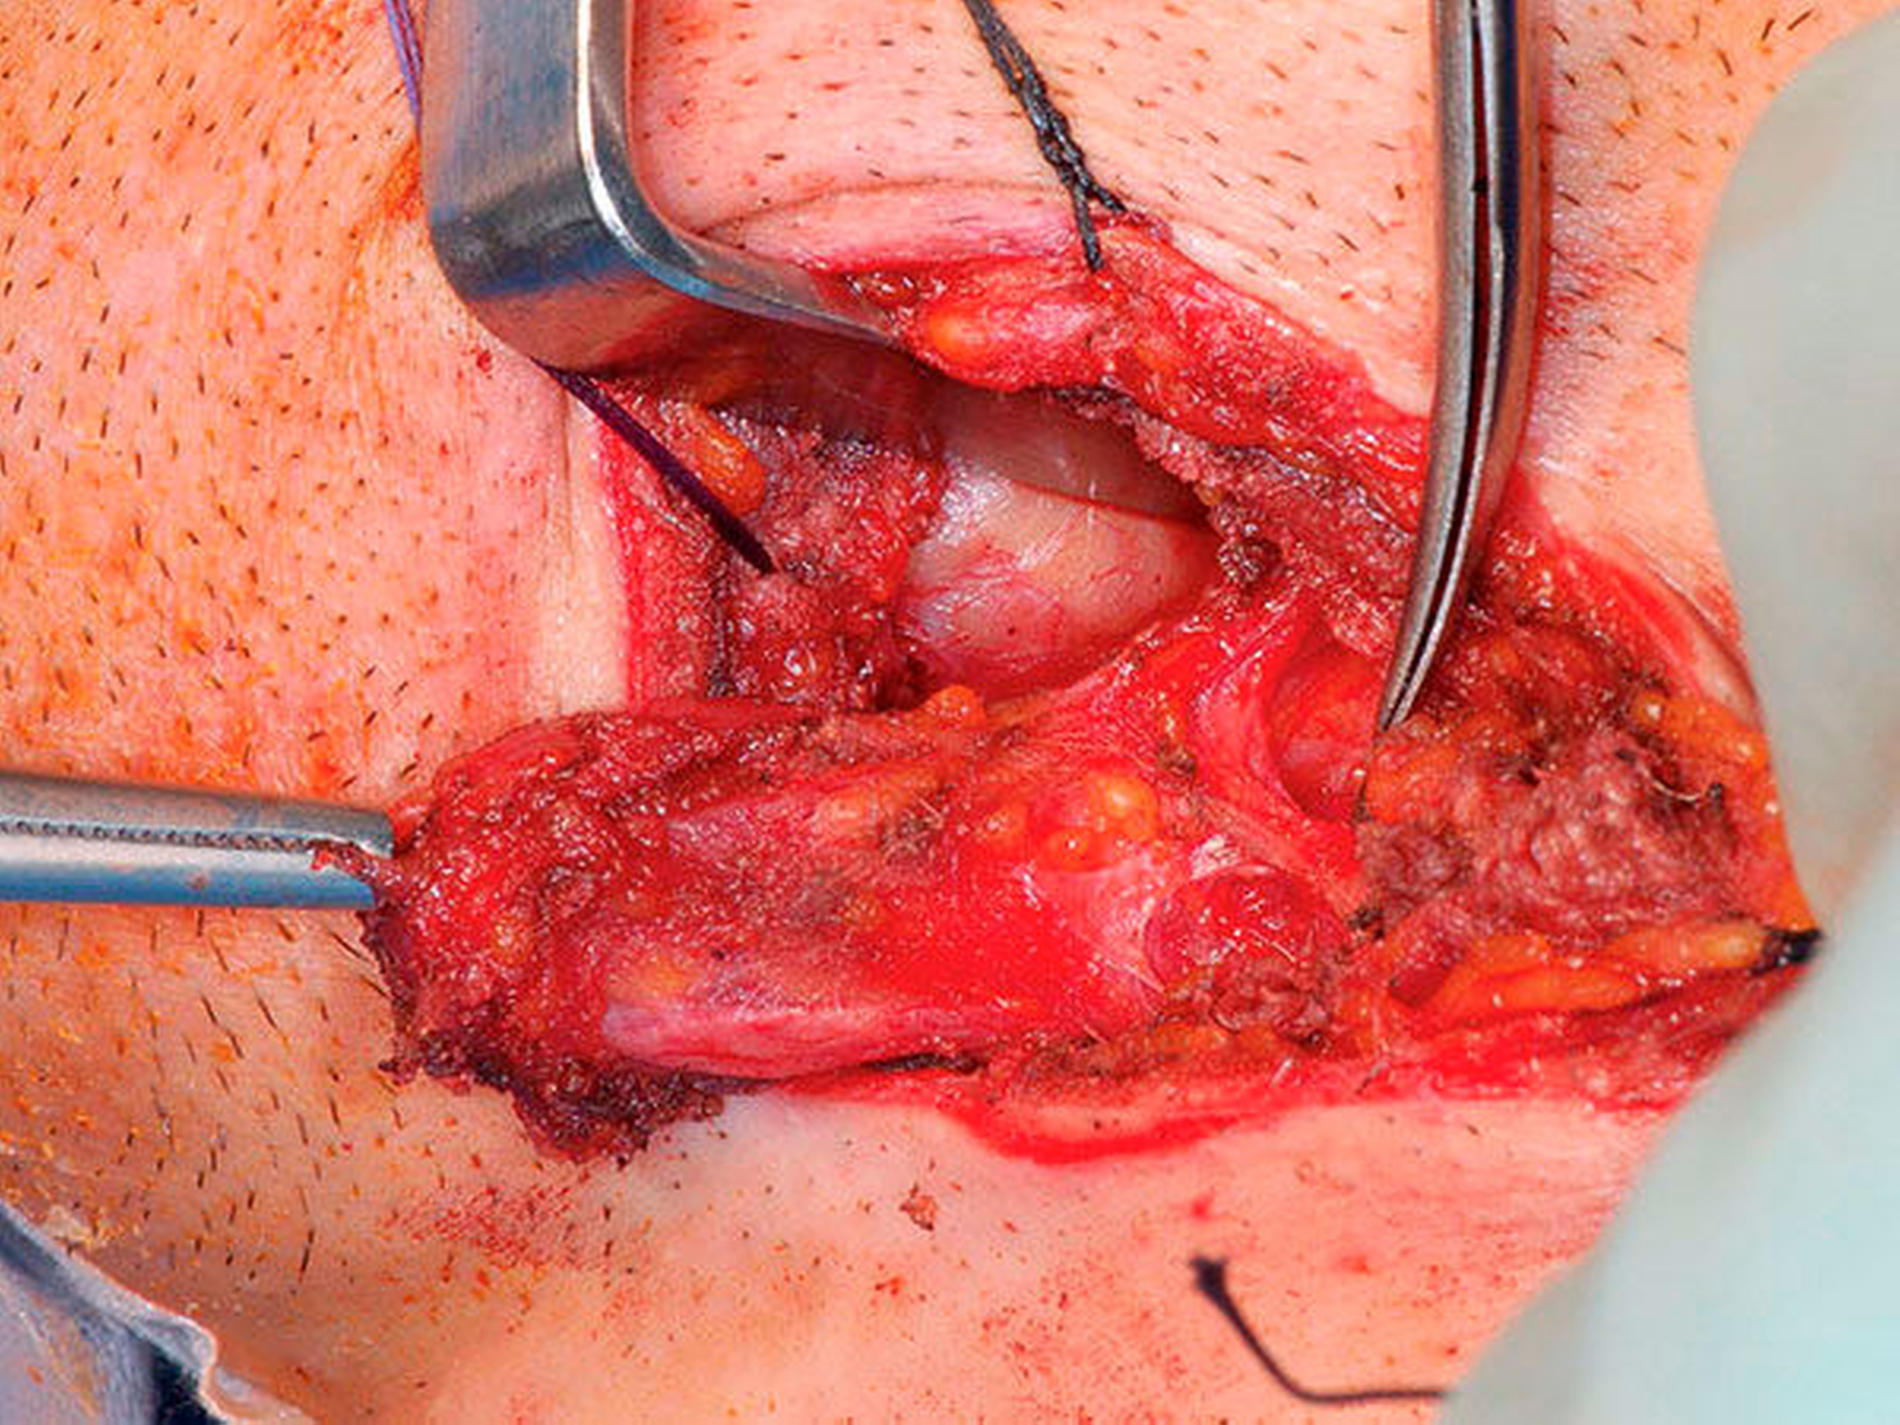

Da die Schwellung nach mehreren Tagen unter antibiotischer Therapie jedoch nicht abnahm und eine weitere diagnostische Abklärung am Präparat sinnvoll erschien, erfolgte die operative selektive Entfernung des Prozesses in einer kurzen Intubationsnarkose (Abbildungen 3 und 4). Bei der Eröffnung des resezierten Präparats entleerte sich putride Flüssigkeit (Abbildung 5).

Sowohl histopathologisch als auch mikrobiologisch (säurefeste Stäbchen mit Nachweis von Mykobakterium tuberculosis) konnte die Verdachtsdiagnose einer Lymphknotentuberkulose verifiziert werden. Im Präparat zeigten sich ausgedehnte eosinophile Nekroseherde mit neutrophilen Granulozyten, Lymphozyten, Epitheloidzellen und einzelne Riesenzellen vom Langhans-Typ ohne einen Nachweis von Malignität. Ebenso konnte bei unauffälligem Röntgen-Thorax und negativen Sputumuntersuchungen eine Lungentuberkulose ausgeschlossen werden.